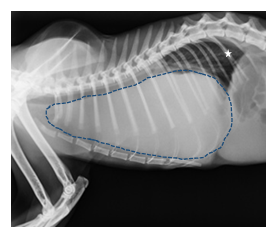

The chest x-ray study of latero-lateral incidence showed an increase in the radiodensity of the cranial thoracic region with soft tissue density, suggestive of cranial mediastinal mass. The presence of pleural effusion was not ruled out.

Figure 1 Chest radiograph, lateral incidence. There is an increase in the radiodensity of the cranial thoracic region with soft tissue density, suggestive of cranial mediastinal mass (dotted line). The lungs are compressed towards the dorsal (white star), which explains the severe dyspnea. The mass does not allow seeing the cardiac silhouette.